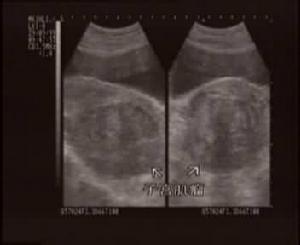

一、超声检查

目前国内B超检查较为普遍。鉴别肌瘤,准确率可达93.1%,它可显示子宫增大,形状不规则;肌瘤数目、部位、大小及肌瘤内是否均匀或液化囊变等;以及周围有否压迫其他脏器等表现。由于肌瘤结节中肿瘤细胞单位体积内细胞密集,结缔组织支架结构的含量及肿瘤、细胞排列不同,而使肌瘤结节于扫描时表现为弱回声,等回声和强回声3种基本改变。弱回声型是细胞密度大,弹力纤维含量多,细胞巢状排列为主,血管相对丰富。强回声型,胶原纤维含量较多,肿瘤细胞以束状排列为主。等回声型介于两者之间。后壁肌瘤,有时显示不清。肌瘤愈硬衰减表现愈重,良性衰减比恶性明显。肌瘤变性时,声学穿透性增强。恶变时坏死区增大,其内回声紊乱。故B超检查既有助于诊断肌瘤,区别肌瘤是否变性或有否恶性变提供参考,又有助于卵巢肿瘤或其他盆腔肿块的鉴别。